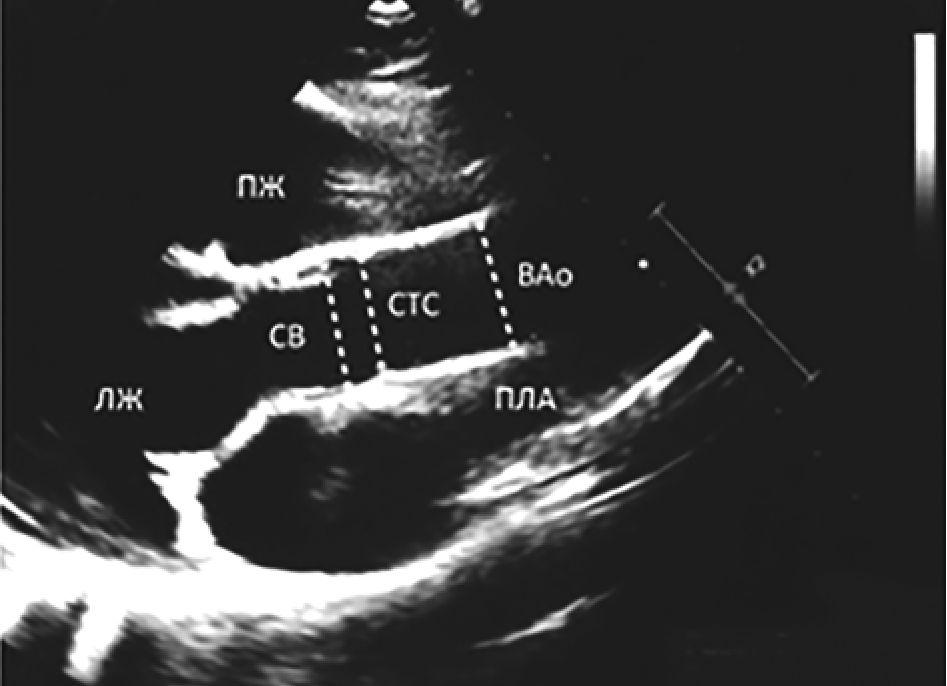

Аорту измеряли по ее внутреннему диаметру на трех основных уровнях (СВ, СТС и ВАо) в систолу в парастернальной позиции по длинной оси левого желудочка (рис. 1).

Рис. 1. Места измерения диаметров аорты в парастернальной позиции по длинной оси левого желудочка (пунктирные линии). СВ - синусы Вальсальвы, СТС - синотубулярное соединение, ВАо - восходящая аорта, ПЖ - правый желудочек, ЛЖ - левый желудочек, ПЛА - правая легочная артерия

Измерения проводили перпендикулярно продольной оси аорты. Размер, превышавший 2 z-score на любом уровне, считали умеренной дилатацией аорты (ДАо), превышение 3 z-score - значительным расширением, а >4 z-score - аневризматической дилатацией.